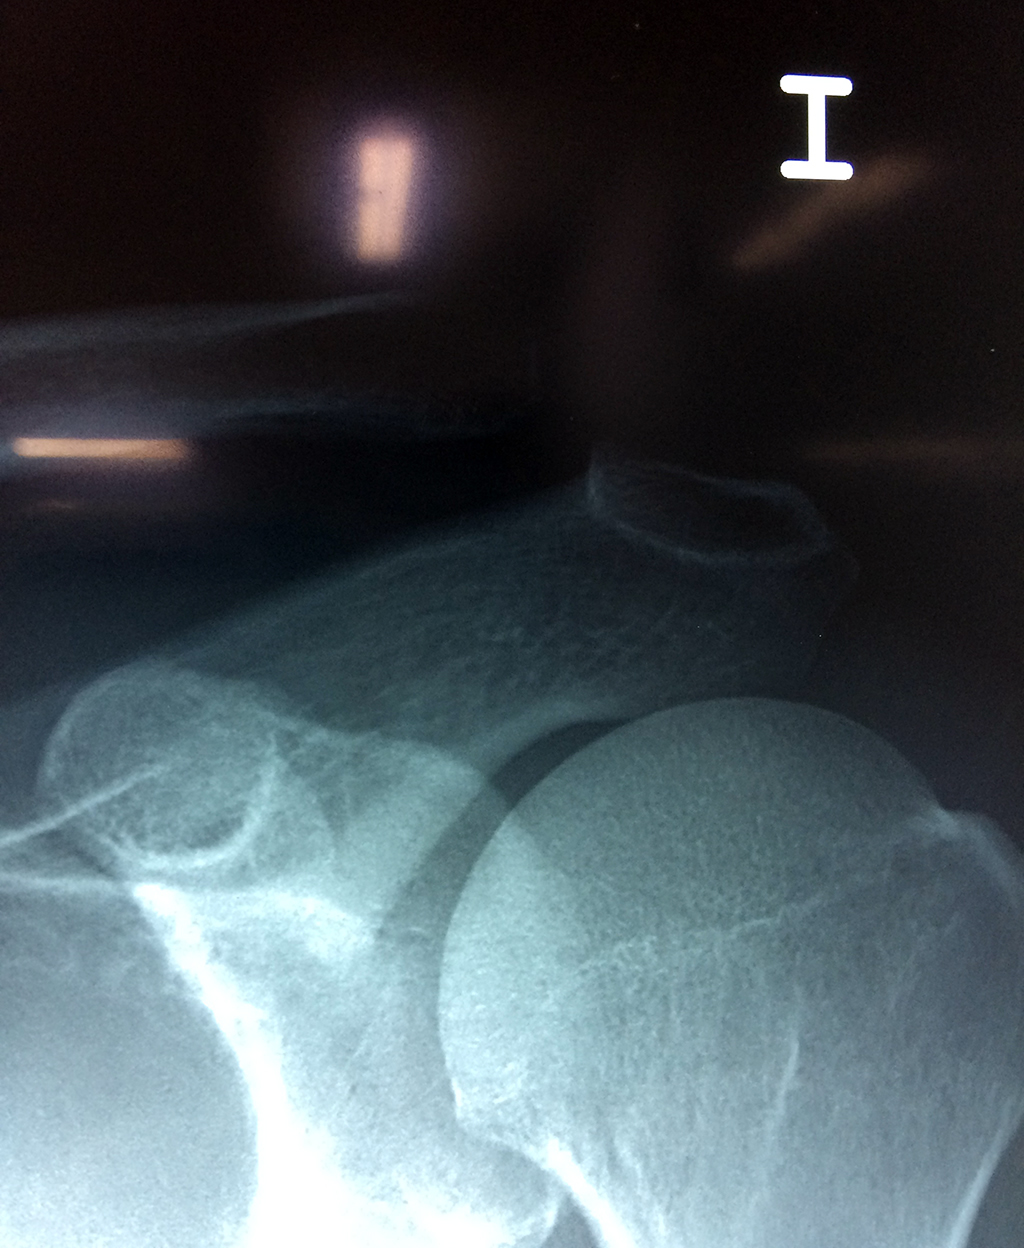

Fémur - Clavícula

La clavícula es un hueso largo, con forma de "S" itálica, situado en la parte anterosuperior del tórax. Junto con la escápula forman la cintura escapular. Se puede palpar por toda su longitud y se extiende del esternón al acromion de la escápula, siguiendo una dirección oblicua lateral y posterior.